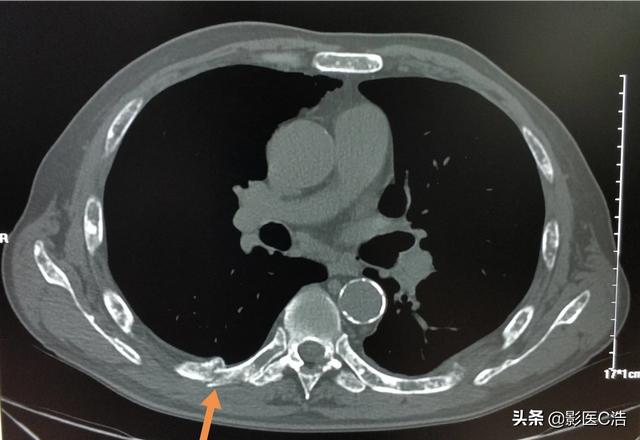

この症例は58歳のゲイ男性で、肩を軽く伸ばしただけで痛みが続くようになり、X線検査で低密度病巣が見つかった:

これは骨転移に基づく軽微な外力による病的骨折であった。穿刺が行われ、病理結果は低分化肺腺癌の骨転移であった。

左肺にあるこの不規則な結節が原発巣で、わずか2.6cmしかない。このような骨転移を伴う肺がんは、もはや手術不可能です。肺がんはあまりにもありふれた病気であり、初期症状の中には非典型的なものや無症状のものさえあるからだ。肺がんの約30%では、転移の症状が最初の症状であり、さらなる肺がんが発見される前に転移が最初に発見される。

これは、当時彼が鎖骨骨折のために受けた内固定手術で、手術をしなければ自然治癒が非常に難しい病的骨折である。